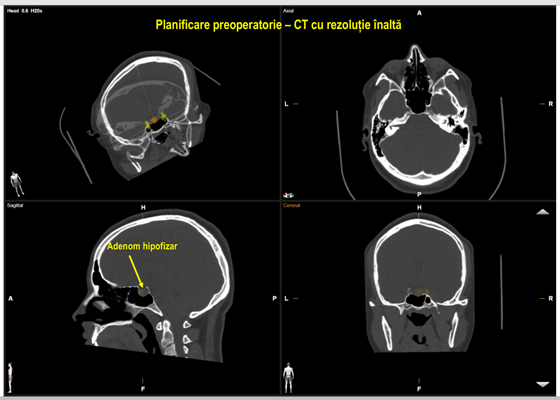

Sinusul sfenoidal și baza craniului în porțiunea anterioară se deosebesc printr-o varietate anatomică vastă, ceea ce face dificilă orientarea spațială în timpul operației. De aceea, s-au depus mari eforturi pentru a asigura precizia actului chirurgical în circumstanțe anatomice dificile. Pentru orientare, chirurgii foloseau radiografiile intraoperatorii, sondele ultrasonografice etc. Cea mai recentă tehnologie este neuronavigația fără cadru stereotaxic, considerată a fi GPS-ul neurochirurgului, disponibilă pentru toți pacienții din Republica Moldova în sala de operații Hybrid a Spitalului Clinic Republican. Acest sistem de neuronavigație a fost folosit și în cazul pacientei respective.